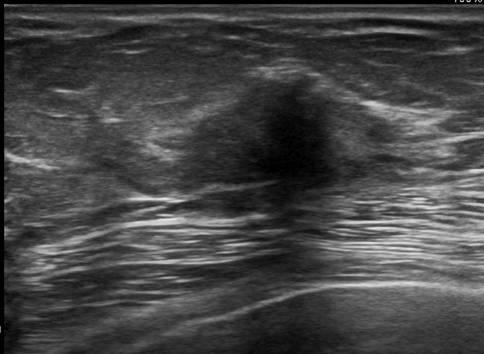

Ung thư vú

» Thông tin: Nữ giới – 76 tuổi.

» Lâm sàng: Khối tuyến vú.